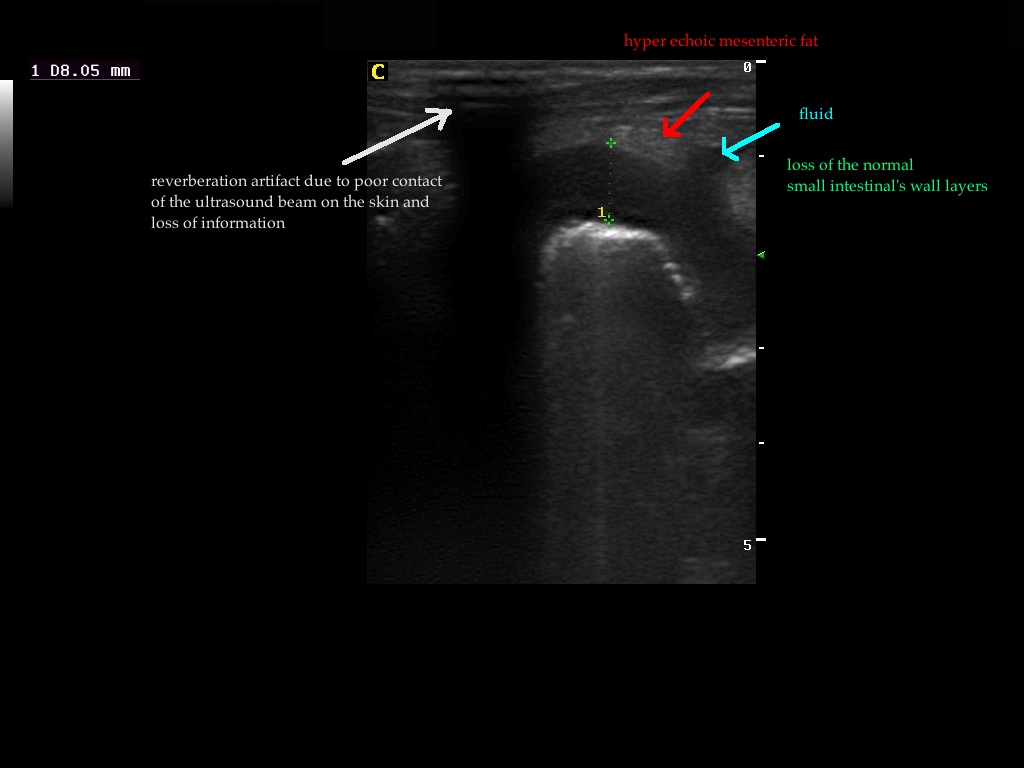

Findings: The ultrasound exam revealed a marked distention of a segment of the small intestine which ended in a narrowed lumen due to a thickened wall. The mesenteric lymph nodes were markendly enlarged and hypoechoic. A fine needle aspirate was performed.

After we decided the path of the needle, the insertion site was prepared with the Hibitane scrub and alcohol. Then we applied some gel on the Linear probe and covered with the elastic glove. Then the syringe was loaded with 5ml of air and attached to the needle. We performed techniques with and without aspiration depending on the blood that sometimes was withdrawn. The diagnosis was Lymphoma.

The GIF shows the frames from the normal small intestinal layering to the thickened abnormal wall in a perpendicular view.